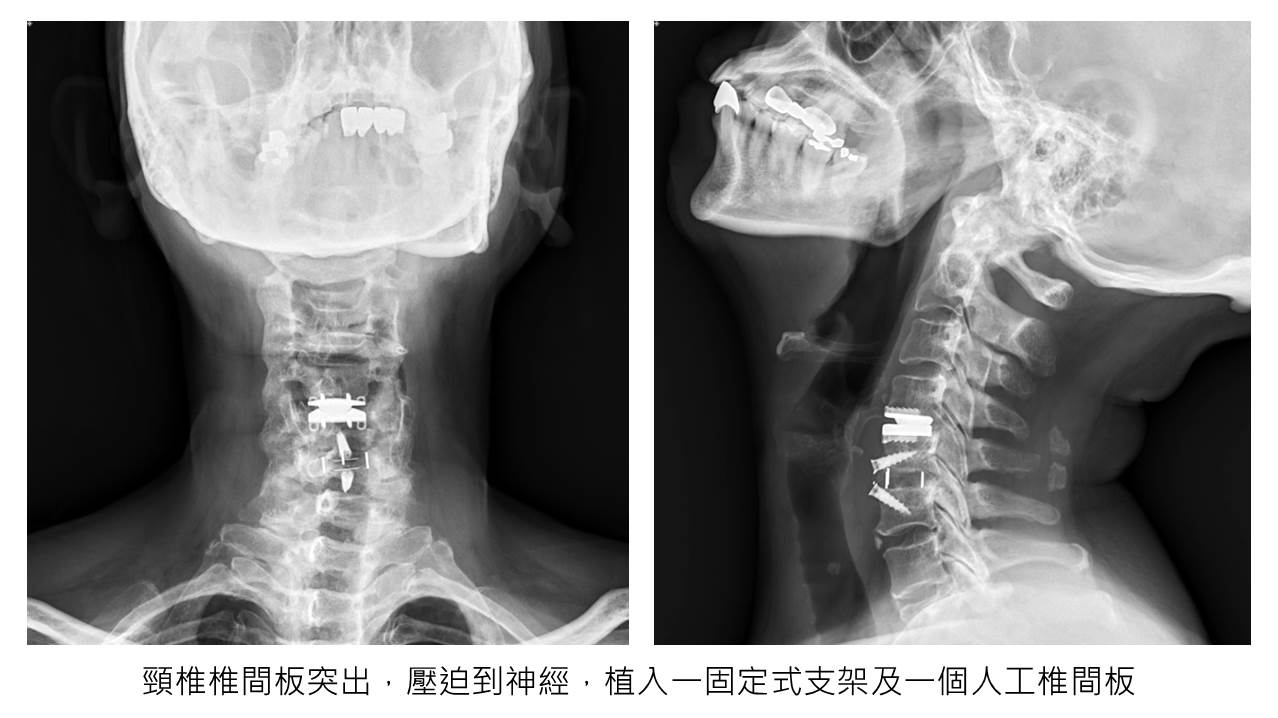

▲X光影像。(照片提供/王大翊)

透過檢查發現,許女士拇趾外翻超過40度,且透過保守治療無法減緩症狀,故透過拇趾外翻矯正手術治療,透過修補軟組織,以及切骨矯正,放鬆拇趾外翻緊繃的韌帶,拉緊內側鬆弛的韌帶,並將往內轉移的大拇趾矯正到理想的角度,術後需練習腳趾抓握訓練、穿鞋墊,才能讓腳維持在正位上,避免病情復發。